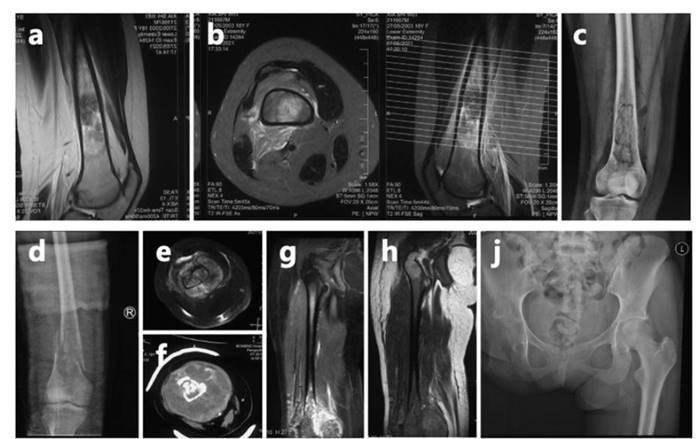

ย้อนกลับไปเมื่อปี 2564 ขณะซือเหว่ยมีอายุเพียง 18 ปี และกำลังเข้าสอบคัดเลือกเข้ามหาวิทยาลัย เธอเกิดเป็นลมหมดสติกลางสนามสอบ แต่เมื่อฟื้นขึ้นมาก็ยังฝืนสอบต่อจนเสร็จ ก่อนจะไปตรวจร่างกายที่โรงพยาบาล และได้รับการวินิจฉัยว่าเป็นโรคมะเร็งกระดูก ซึ่งมีการลุกลามอย่างรวดเร็ว

ในที่สุด แม่ของซือเหว่ยยอมพาเธอไปรักษาที่โรงพยาบาลในกรุงปักกิ่ง แต่อาการกลับทรุดลงอย่างต่อเนื่อง จนหลังผ่านไปประมาณ 1 ปี แพทย์จำเป็นต้องตัดขาข้างขวาของเธอออก เพื่อรักษาชีวิตเอาไว้

อย่างไรก็ตาม ในช่วงปี 2566-2567 แพทย์ตรวจพบว่ามะเร็งของซือเหว่ยกลับมาเป็นซ้ำที่ปอด และเมื่อไม่นานมานี้ ยังพบเนื้องอกใหม่ในเยื่อหุ้มปอดอีกครั้ง แม้ต้องเผชิญข่าวร้ายซ้ำแล้วซ้ำเล่า แต่เธอยังคงเลือกมองโลกในแง่ดี